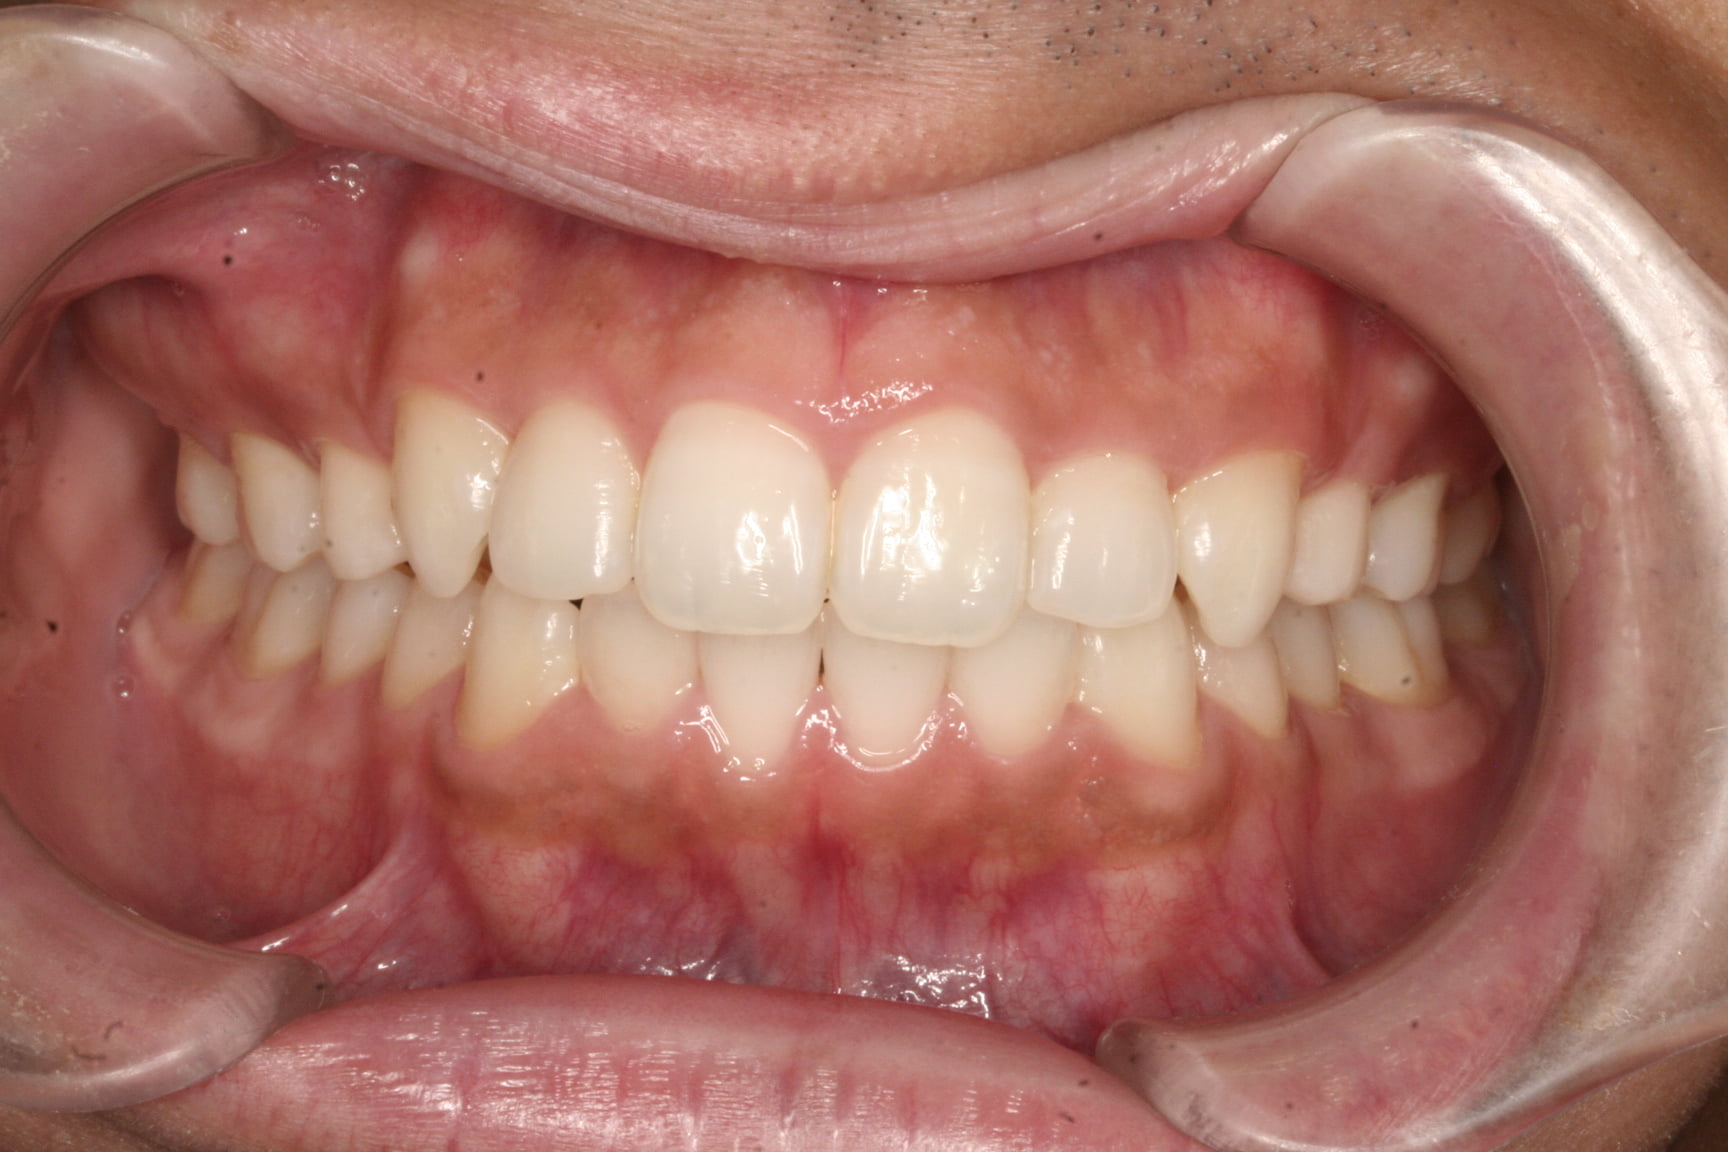

出っ歯を治したい

年齢層 20代

性別 女性

主訴 【主訴】出っ歯を治したい 【診断・症状】上下凸凹、開咬、口元が出てる

治療費用 検査・診断:38,500-/裏側矯正治療:1,397,000-(※全て税込)

治療期間 約2年(26回)

抜歯 有(上4,4)

矯正の装置 裏側矯正(舌側矯正)

副作用、リスク 歯肉退縮,歯根吸収,疼痛,咬合の違和感,装置の違和感,虫歯,歯肉炎

case14_出っ歯_after

After